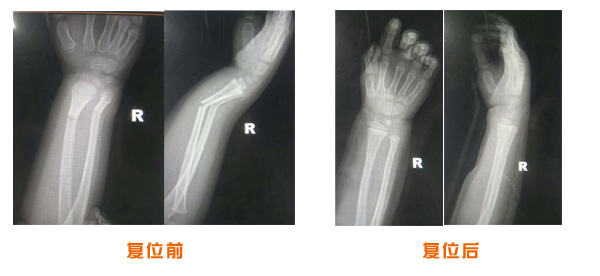

復位前后對比

尺橈骨骨折治療前后

尺橈骨克雷氏骨折治療前后